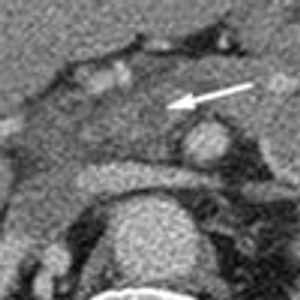

A 43-year-old white man presented to the emergency department with dyspnea, abdominal bloating, fever with chills, night sweats, decreased oral intake, and myalgia of 1 week's duration. He was found to have heart failure caused by systolic dysfunction. Viral myocarditis was the presumptive diagnosis after investigation for other causes.